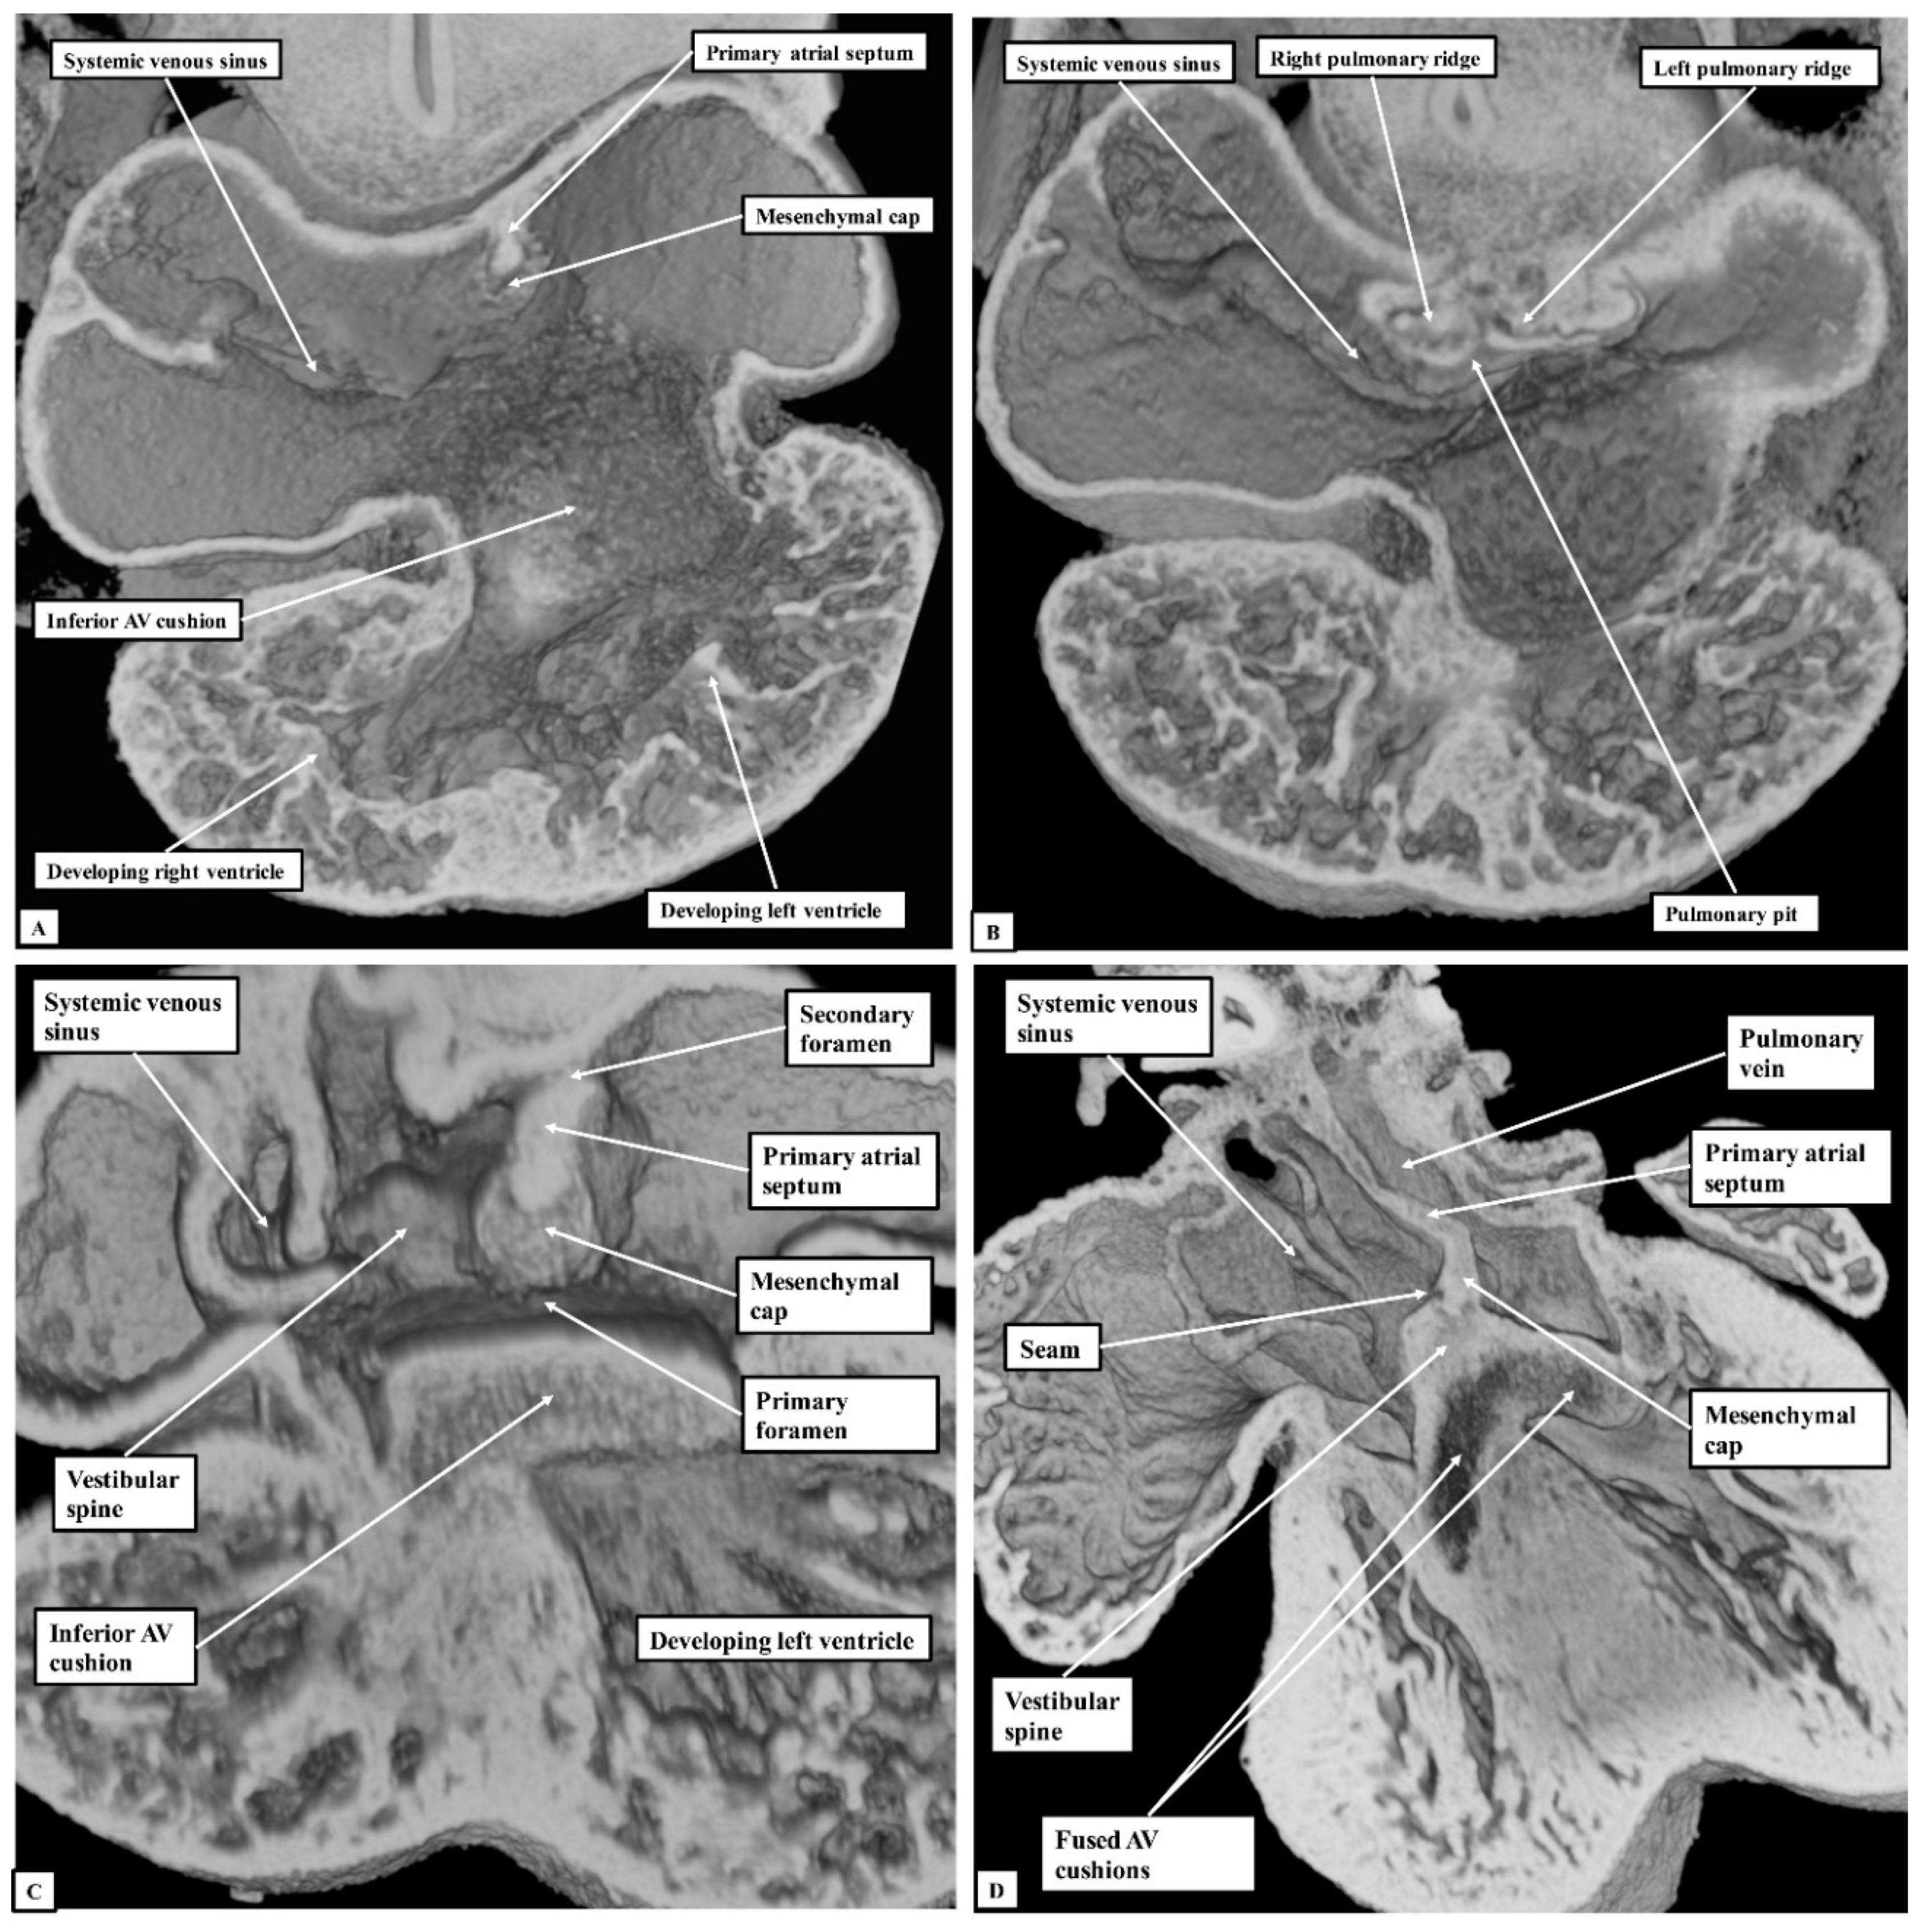

Figure 7. The images show the features of the vestibular defect, as was found in four of the datasets. The dataset used to prepare the figure is sectioned so as to show the appearance of the defect in the four-chamber plane (Panel A), and as seen from the right (Panel B) and left (Panel C) sides. The double-headed white arrow in the left-hand panel shows the margins of the oval fossa. AV—Atrioventricular.

If development proceeds in a normal fashion, the margins of the oval fossa are intact by E15.5. We examined episcopic datasets prepared from 48 mouse embryos at this stage. In 38 of the mice, the findings show the normal arrangement, with the primary septum folded on itself cranially, its length being considerably greater than the length of the fossa (Figure 6A). In these 38 datasets, the vestibular spine and mesenchymal cap fused together to form the caudal rim of the fossa, with obliteration of the seam initially seen between the two components during E13.5 (Figure 5D). The primary septum now forms the floor of the oval fossa, with the space between its cranial margin and the atrial roof forming the oval foramen, or secondary atrial foramen. The excessive length of the septum relative to the dimensions of the fossa provides the mechanism that permits closure of the foramen subsequent to birth. In 10 of the datasets prepared from mice sacrificed at E15.5, however, we found deficiencies of either the inferior rim of the oval fossa, or the attachment of the leading edge of the primary septum. In two, the findings could be attributed to the failure of formation of the vestibular spine (Figure 6B), with additional failure of growth of the primary septum in one of the two. In both, the lack of growth of the spine was associated with persistence of a common atrioventricular junction, with the atrioventricular cushions fused to each other, and also to the crest of the muscular ventricular septum, in other words producing an “ostium primum” defect. In four further datasets, although the vestibular spine had protruded in anticipated fashion to form the caudal margin of the oval fossa, thus separating the right and left atrioventricular junctions and forming the caudal rim of the fossa, the primary septum itself was deficient adjacent to the caudal rim, thus producing a hole in the floor of the fossa adjacent to its antero-inferior buttress, in other words, an “ostium secundum” defect (Figure 6C) The defect was large in two of the datasets but smaller in the remaining two. In the remaining four datasets, the mesenchymal cap had failed to fuse with the vestibular spine. The spaces in the floor of the oval fossa in these four hearts (Figure 7), therefore, are directly comparable to the vestibular defects found in our autopsied hearts.